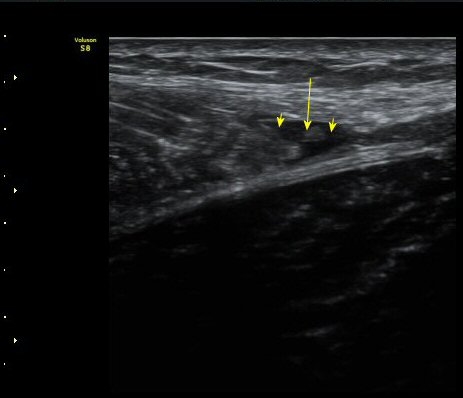

ÃÊÀ½ÆÄ °Ë»ç

¼ö»ó ÈÄ 2ÀÏ Â°

³»Ãø ºñº¹±Ù Á¾´Ü¸é°Ë»ç¿¡¼­ ±ÙÀ°°ú ÈûÁÙ ÀÌÇà ºÎÀ§¿¡ ÀÛÀº ÆÄ¿­°ú ¼ö¾× Àú·ù, ÆÄ¿­ µÈ

±ÙÀ°ÀÇ ±ÙÀ§ºÎ·Î ´ç°ÜÁüÀÌ °üÂû µÊ(±×¸² 1, 2, 3).